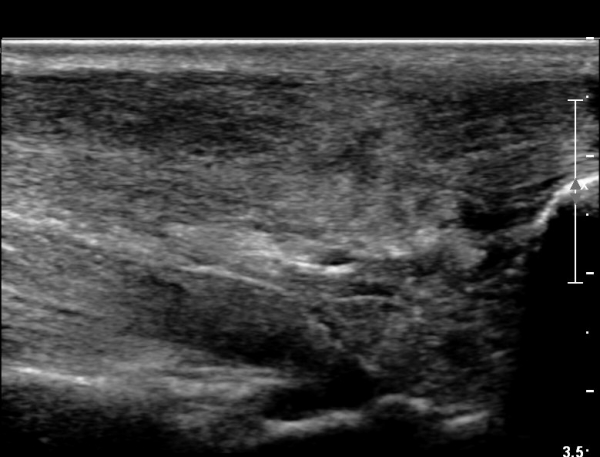

¾ÆÅ³·¹½º°Ç ±ÙÀ§ºÎ Á¾´Ü¸é°Ë»ç¿¡¼­ ¾ÆÅ³·¹½º°ÇÀÇ Àú¿¡ÄÚºÎÁ¾, ±¹¼ÒÀû ¿¬°á¼º ¼Ò½ÇÀÌ °üÂûµÇ¾î

ÆÄ¿­ÀÌ ±¤¹üÀ§ ÇÑ °ÍÀ» º¸¿©ÁÜ(»çÁø 6, 7).

¾ÆÅ³·¹½º°Ç Ⱦ´Ü¸é°Ë»ç¿¡¼­  ¾ÆÅ³·¹½º°ÇÀÇ Àú¿¡ÄÚºÎÁ¾, ±¹¼ÒÀû ¿¬°á¼º ¼Ò½ÇÀÌ °üÂûµÊ(»çÁø 8).